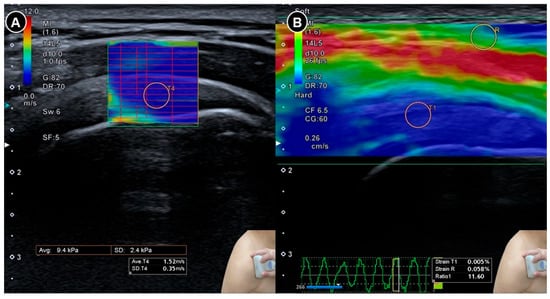

Figure 8. Sonoelastography of the supraspinatus tendon. Shear wave elastography (A) demonstrates the shear wave speed and strain elastography (B) illustrates the strain ratio. The figure was redrawn by the authors with reference to Yun et al. [37].

Wu and colleagues [36] examined the elasticity of the coracohumeral ligament using shear wave elastography in 20 patients with clinically suspected adhesive capsulitis and 30 healthy individuals (Figure 7). Measurements of ligament thickness and stiffness were taken from both shoulders in the neutral position and under maximal external rotation. Among the patients, the symptomatic shoulders showed significantly greater coracohumeral ligament thickness (p < 0.001) and a higher elastic modulus in the neutral position (median 234.8 kilopascals, interquartile range 174.4 to 256.7) compared to the asymptomatic side (median 203.3 kilopascals, interquartile range 144.1 to 242.7; p = 0.004). However, this difference was not statistically significant under maximal external rotation (p = 0.123).

Yun and colleagues [37] conducted a prospective case-control study involving 25 symptomatic shoulders from 20 patients with adhesive capsulitis and 24 asymptomatic shoulders from 18 individuals as controls. Both shear wave and strain elastography were performed on the supraspinatus and infraspinatus tendons. In patients with adhesive capsulitis, the mean velocity and stiffness were significantly higher (p < 0.001), while the strain ratio (defined as strain in the subcutaneous fat divided by strain in the target tendon) was significantly lower (p < 0.001) than in the control group (Figure 8). Receiver operating characteristic curve analysis showed excellent diagnostic accuracy, with area under the curve values exceeding 0.970 for both tendons. Subsequently, Chang et al. [38] raised concerns regarding the interpretation of the strain ratio whereby they pointed out that in normal physiology, tendons are stiffer than subcutaneous fat and therefore exhibit less strain, which should result in a strain ratio greater than 1. However, the reported median strain ratio of the supraspinatus tendon in the control group was 0.38, suggesting an inconsistency in either the calculation or interpretation of the strain values. This discrepancy underscores the need for standardized reporting conventions in elastography studies.